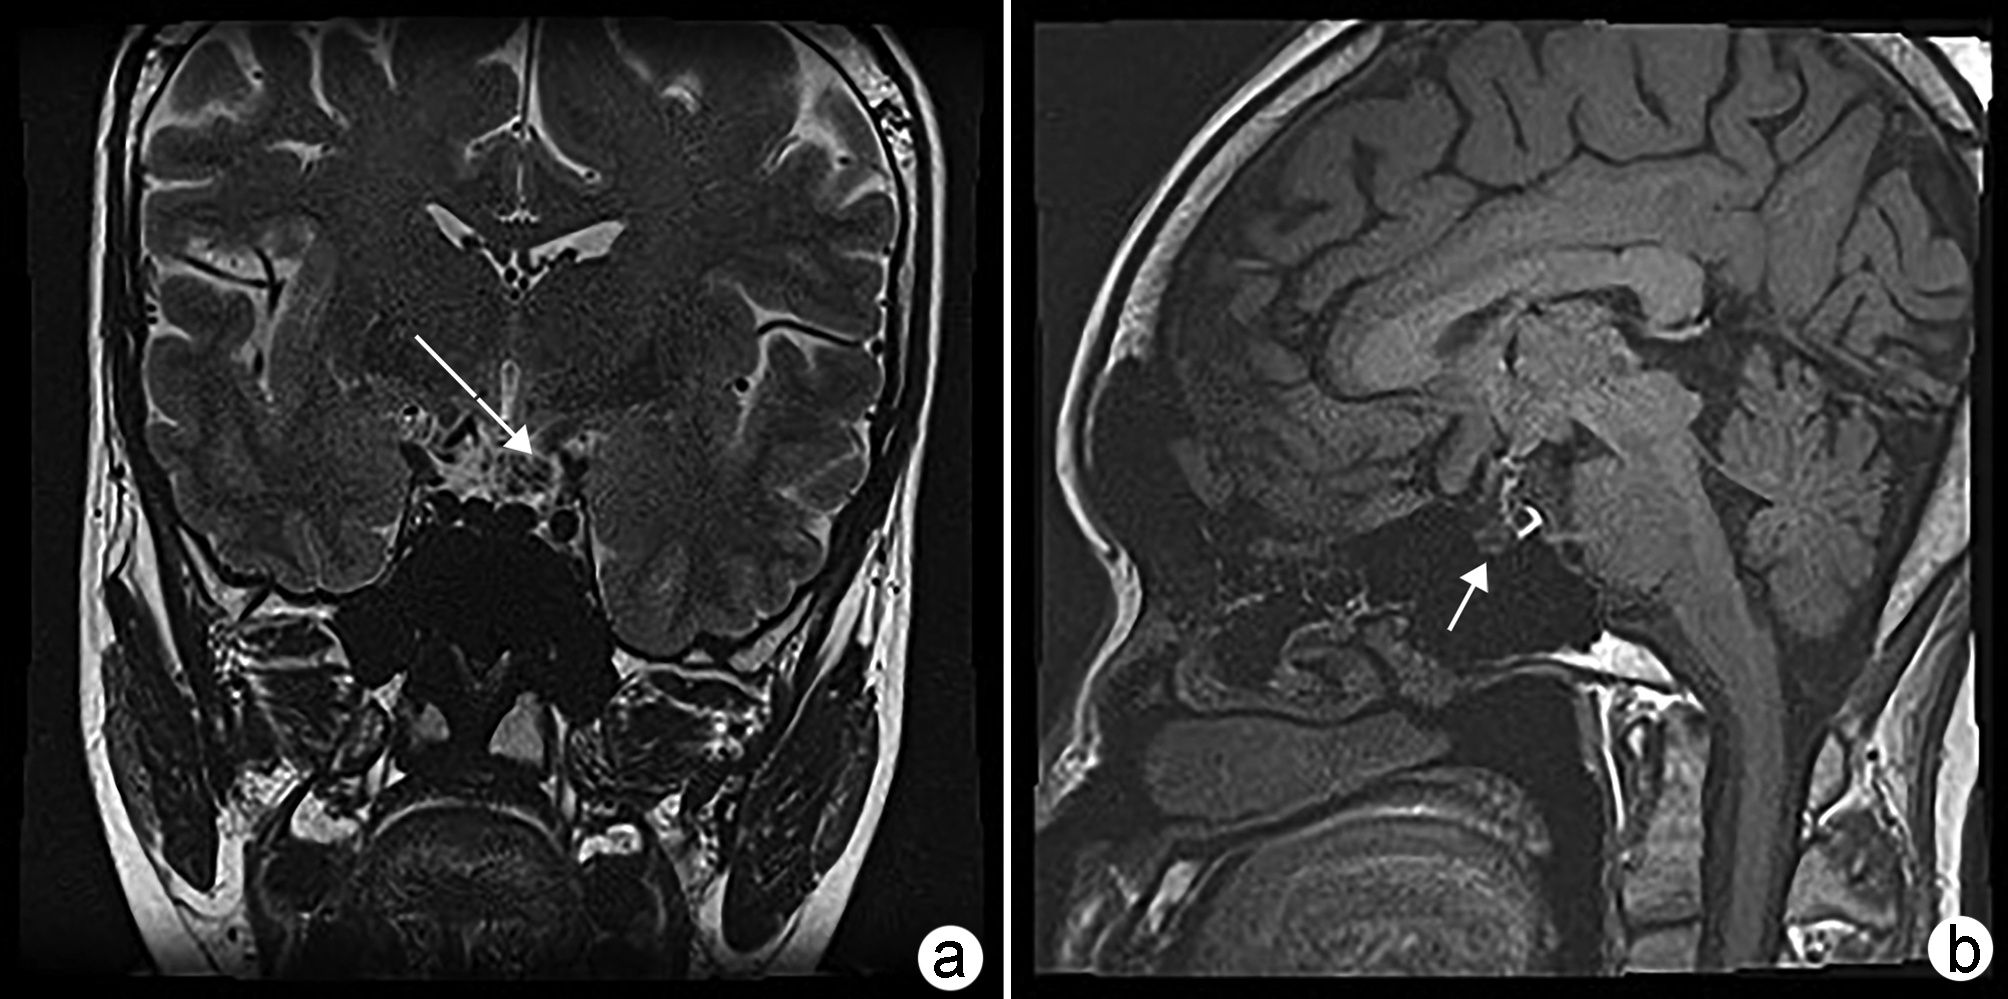

Risk factors for cognitive impairment associated with nonalcoholic fatty liver disease

Cheng ZHOU, Ran JIA, Jingjing WEI, Chenlu ZHAO, Dongfang SHANG, Wenxia ZHAO

2022, 38(11): 2592-2595. DOI: 10.3969/j.issn.1001-5256.2022.11.031

Abstract(806) HTML (299) PDF (1863KB)(59)

Abstract:

At present, non-alcoholic fatty liver disease (NAFLD) has become one of the most common chronic liver diseases in the world. Recent studies have shown that varying degrees of central nervous system dysfunction can occur during the progression of NAFLD, including cognitive impairment and emotional imbalance. This article summarizes the main risk factors for NAFLD-related cognitive impairment at different stages, so as to provide a basis and ideas for the early prevention and clinical treatment of this disease.